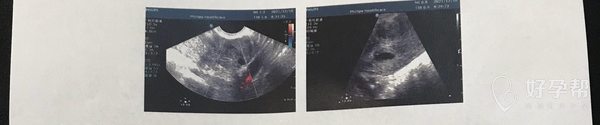

您好大夫,11月17日试管2个胚胎,12月10日一超显示宫内偏右宫角一个孕囊,13✖️7mm,内有卵黄囊,左边提示有个偏实性包块,11✖️11mm,内有不均质略低回声,cdfi周围可见少许点状血流信号,报告写的可能是增生输卵管?(之前造影通而不畅伴粘连),比较担心,另一个有没有宫外的可能?hcg翻倍正常,目前已经大于1万